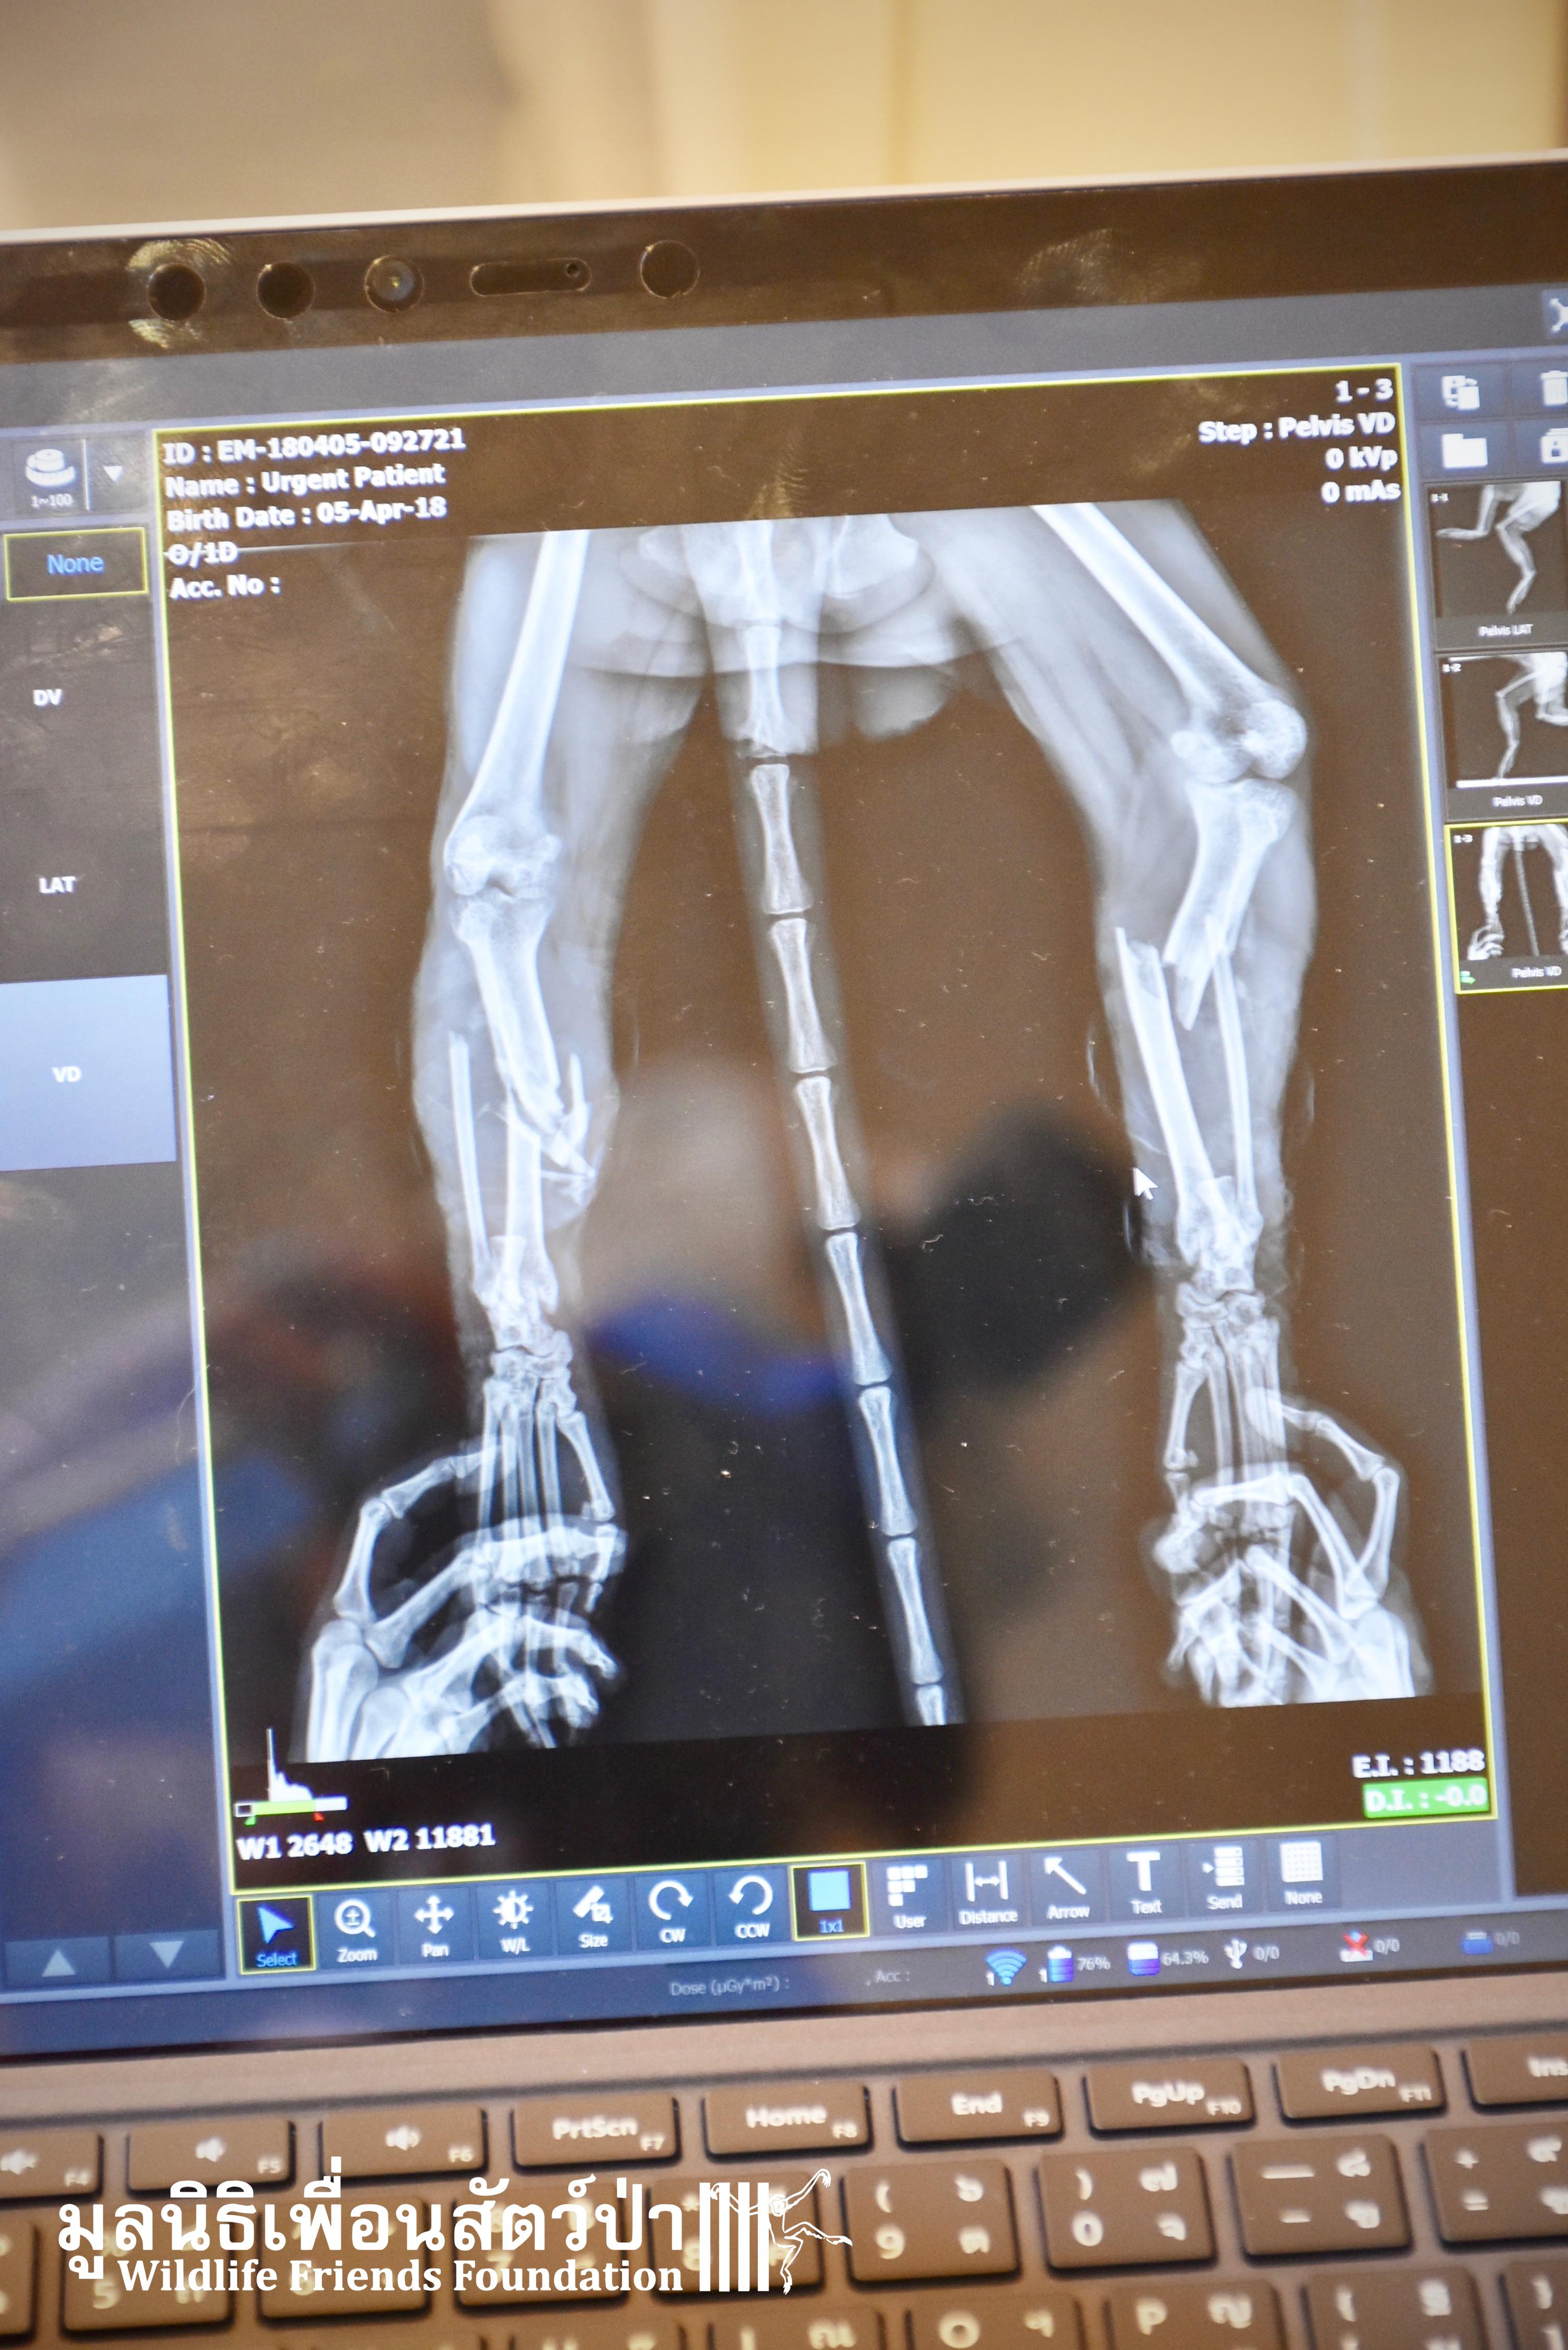

Last week we received a call from help from some veterinary colleagues at a pet hospital in Bangkok who had received a severely injured adult male long-tailed macaque (Macaca fascicularis) who had been found by a lady in Ayutthaya. She informed the staff at the Crystalpet Hospital in Bangkok that the monkey had been dumped at the temple as an unwanted pet. She had seen him unable to move sat in a shallow pond for sometime and got worried. The lady captured him and rushed him straight to the clinic who asked if we could house him at the WFFT Wildlife Rescue Centre. After a full health check it was found the ‘Jok’ as we have called, had two very badly broken legs. We do not know what caused this but it was sure a huge incident as the breaks in his legs were very severe as you can see from the x-rays. Two days ago the WFFT Vet Team were joined by a group of other veterinarians, orthopaedic surgeons, who came to fix his legs using metal plates and pins. The surgery went well and for now Jok is recovering well at the WFFT Wildlife Hospital. We will keep you posted on his progress.